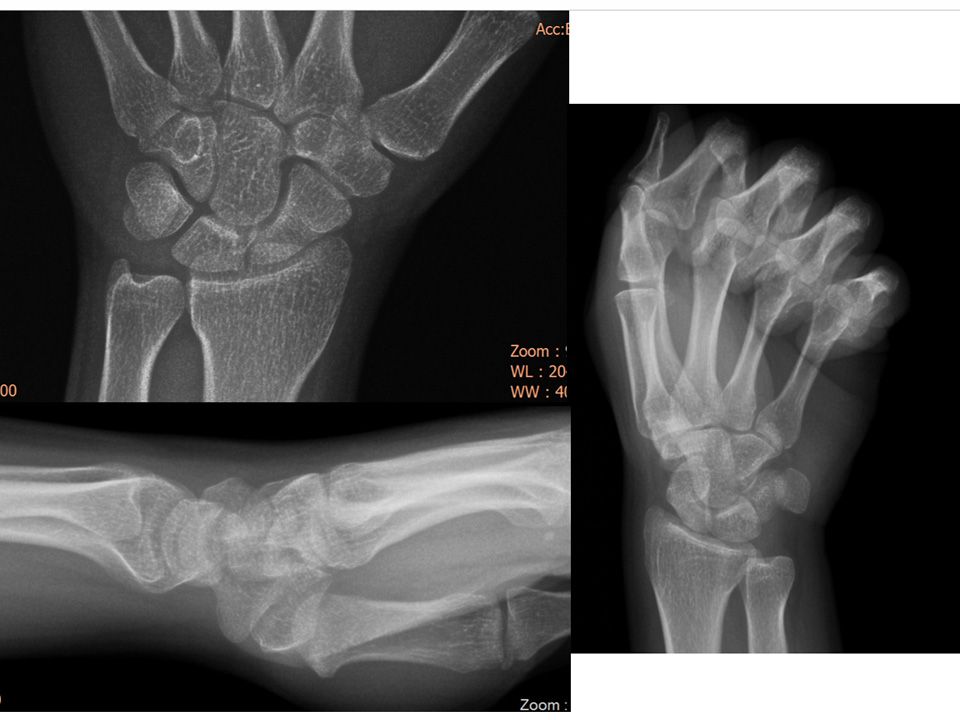

22 yaş, kadın, ev hanımı, sağ el dominant2 yıl önce düşme sonrası sağ el bileği dorsal ağrısıFTR, istirahat ateli ve NSAID’e rağmen geçmemişParmak ekstansiyon testi +